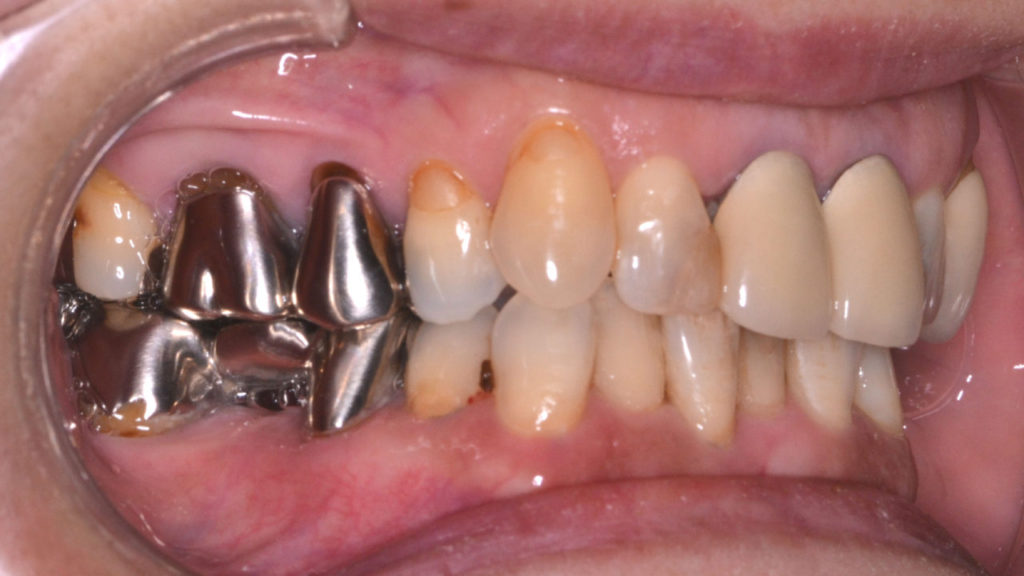

治療前

奥歯が干渉している状態